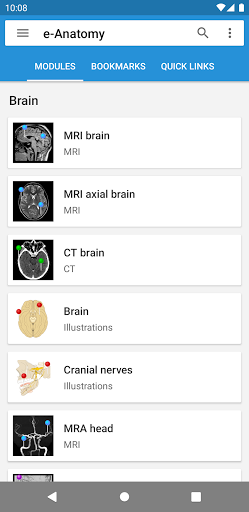

وحدات جديدة للمستخدمين المتميزين:

- التصوير بالرنين المغناطيسي الطبيعي للمدارات

- أطلس تشريح الحوض والأنثى للجهاز التناسلي وحدة

جديدة لجميع المستخدمين:

- أطلس تشريح الأسنان

وحدات جديدة للمستخدمين المتميزين:

- التصوير المقطعي المحوسب

للشعاع المخروطي الطبيعي للأسنان - أطلس تشريح الأذن

وحدات جديدة للمستخدمين المتميزين:

- التصوير بالرنين المغناطيسي

العادي لأرقام اليد - التصوير بالرنين المغناطيسي العادي للإبهام

وحدات جديدة لجميع المستخدمين:

-التشريح الجراحي لاستئصال باطنة الشريان السباتي